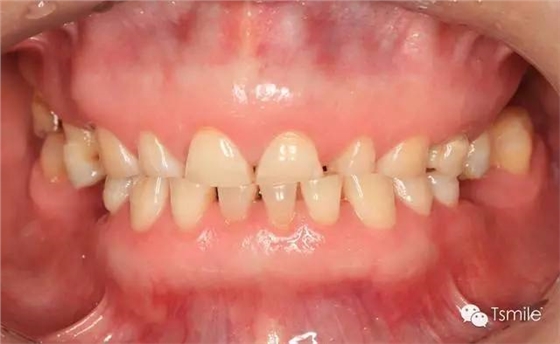

圖1: 夜磨牙導(dǎo)致的牙列重度磨耗